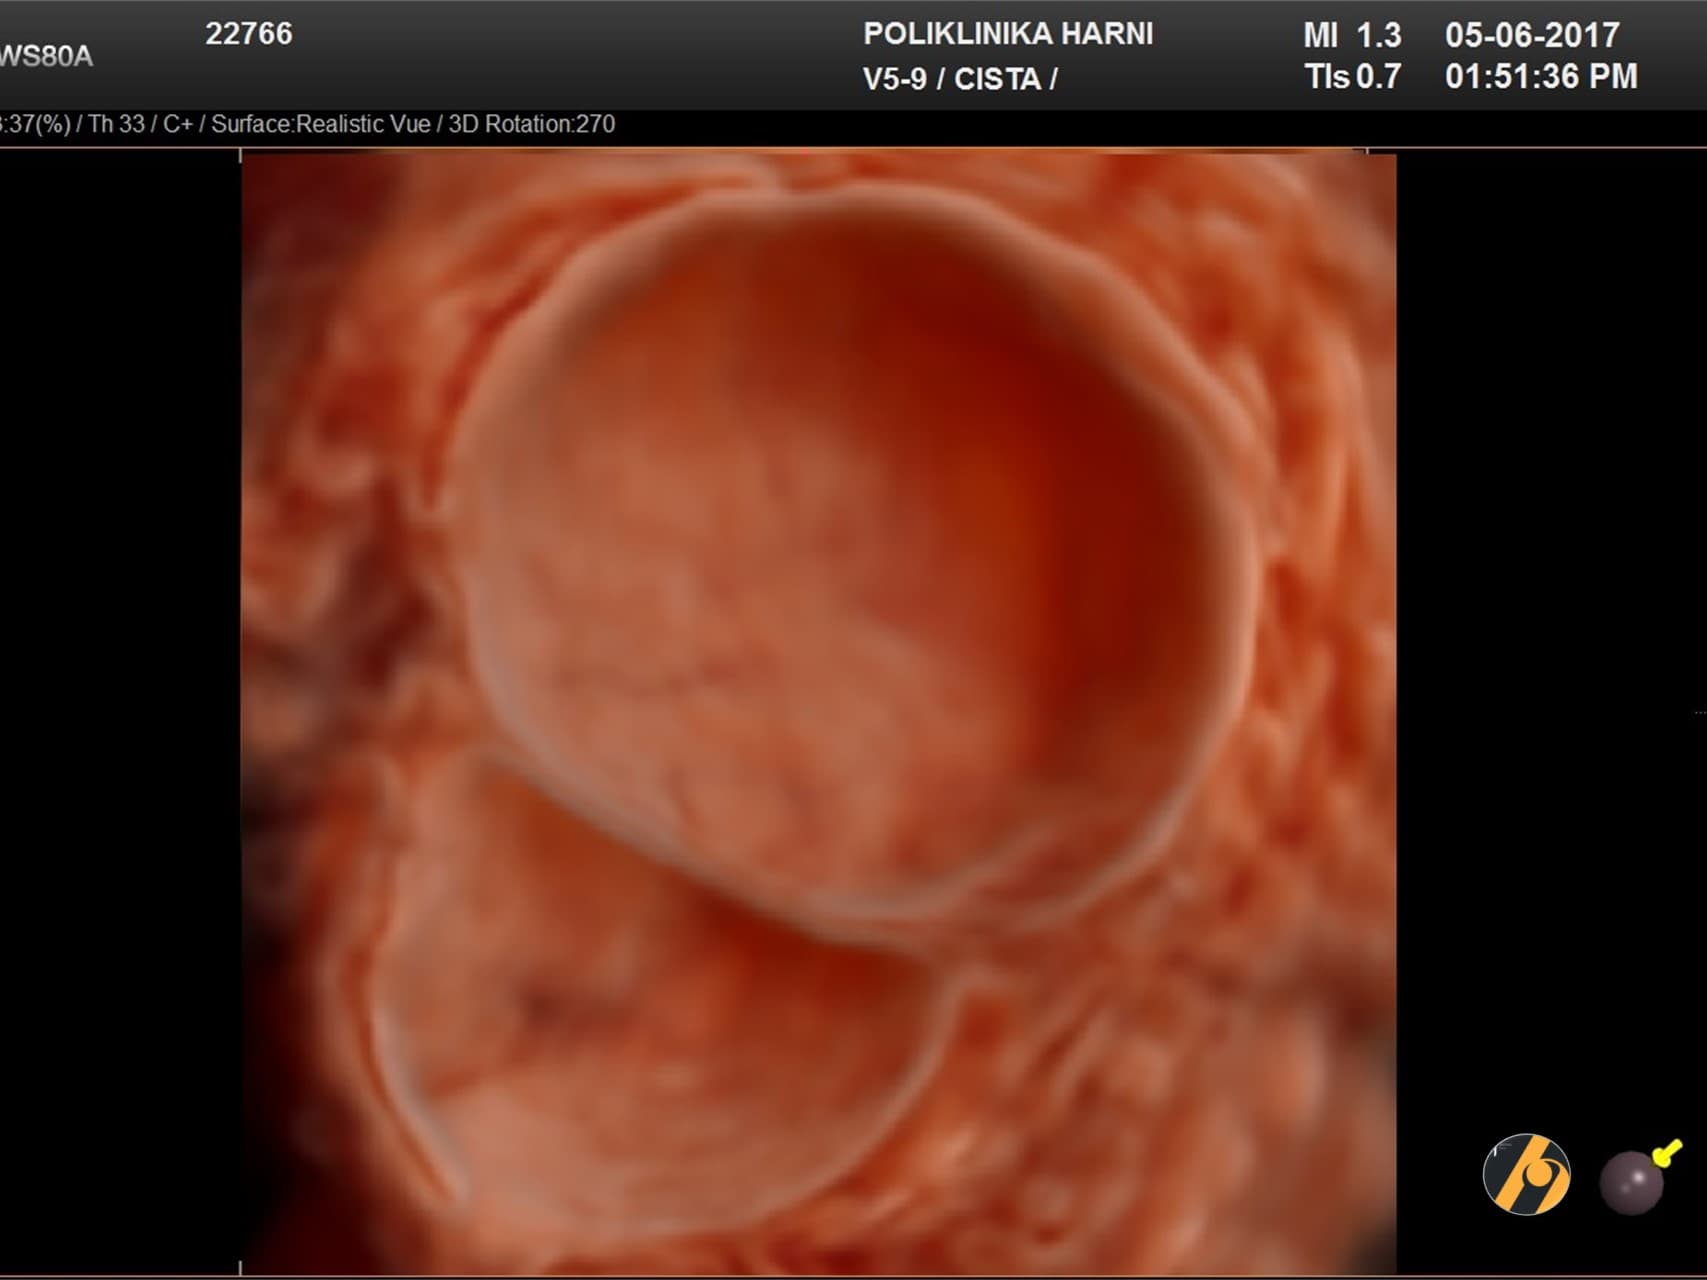

- Zloćudni serozni tumori / cistični karcinomi jajnika. Zloćudne ciste se javljaju kao oblik karcinoma jajnika. Karcinom se javlja kod 20 od 100 000 žena. Zloćudne ciste se razlikuju svojim izgledom od dobroćudnih. Takve ciste obično sadrže više šupljina, izdanke u unutrašnjosti ciste te druge značajke koje mogu upućivati na zloćudni proces.